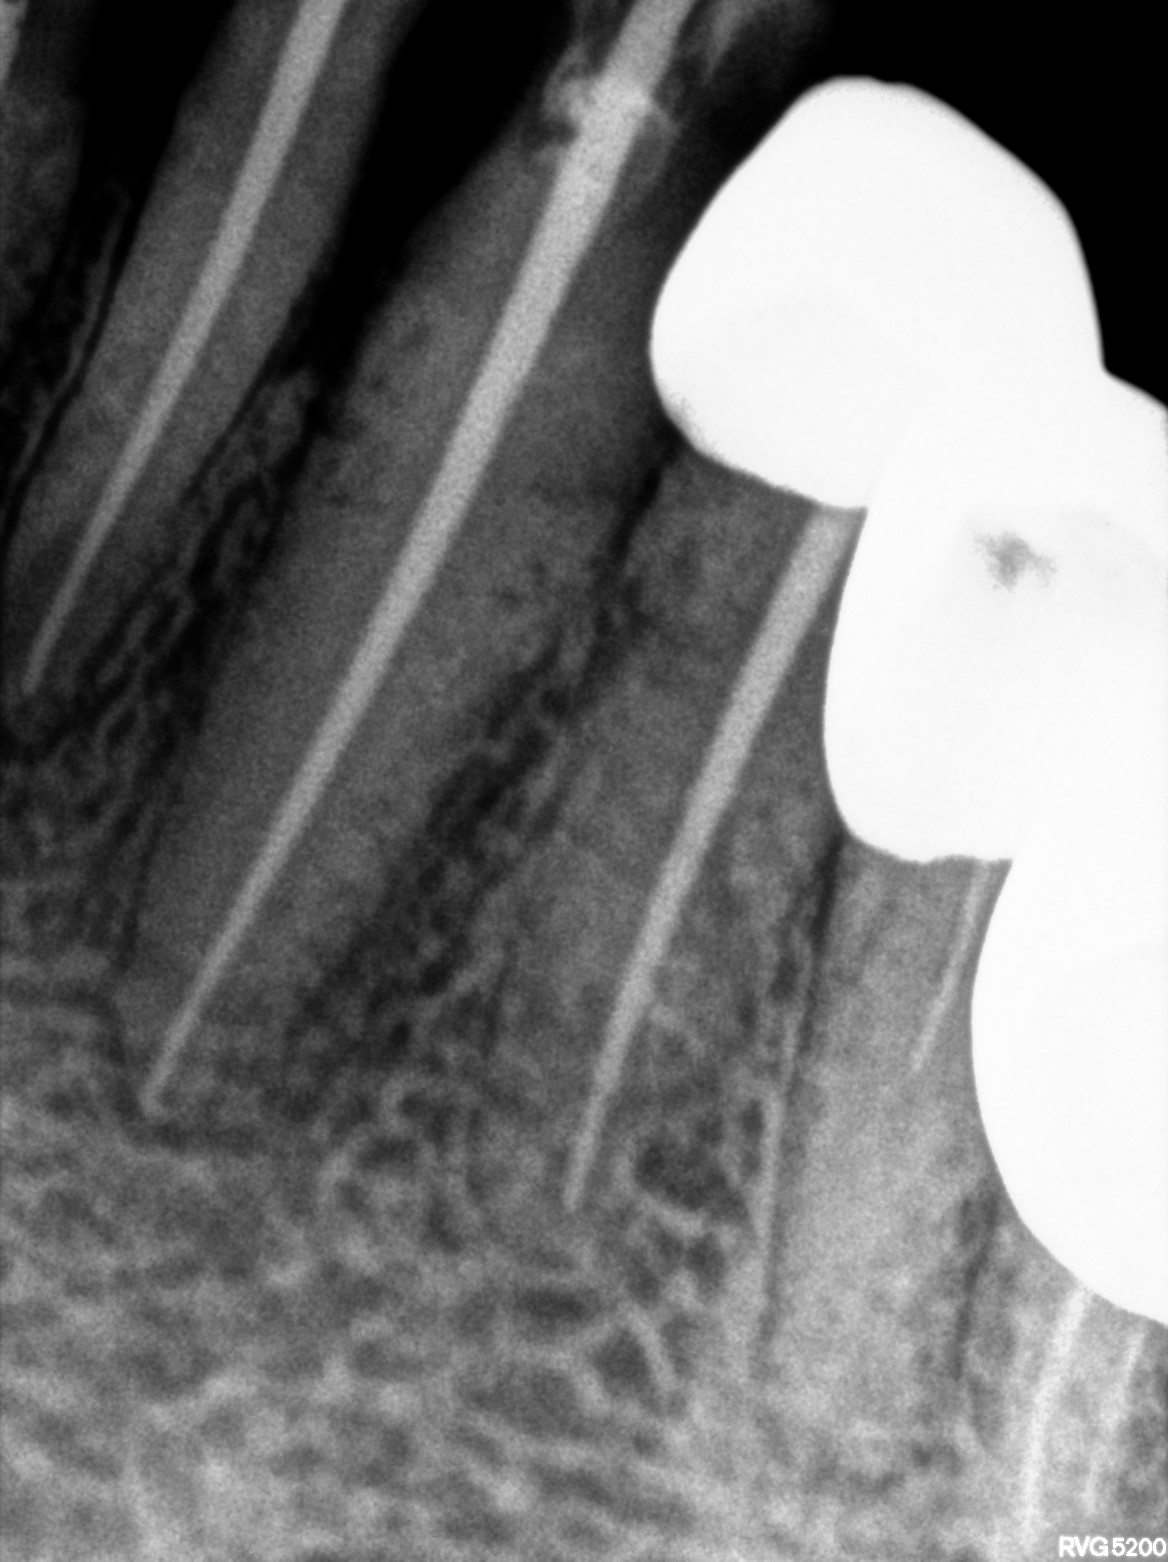

Dental Radiographs FHIR: DocumentReference · LOINC 24641-7

d (1).jpg

24641-7

xray_1772525715_0.jpg